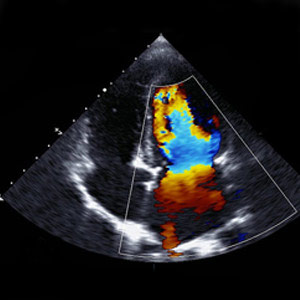

Echocardiography (ECHO)

Echocardiogram Test in South Kolkata uses high frequency sound waves from a hand-held wand placed on your chest to take pictures of your heart’s valves and chambers. This ultrasound test checks the structure and function of your heart. Echo is generally recommended to check your heart’s condition when you show symptoms like shortness of breath, chest pain, or detect any congenital heart defects before birth.

Color Doppler